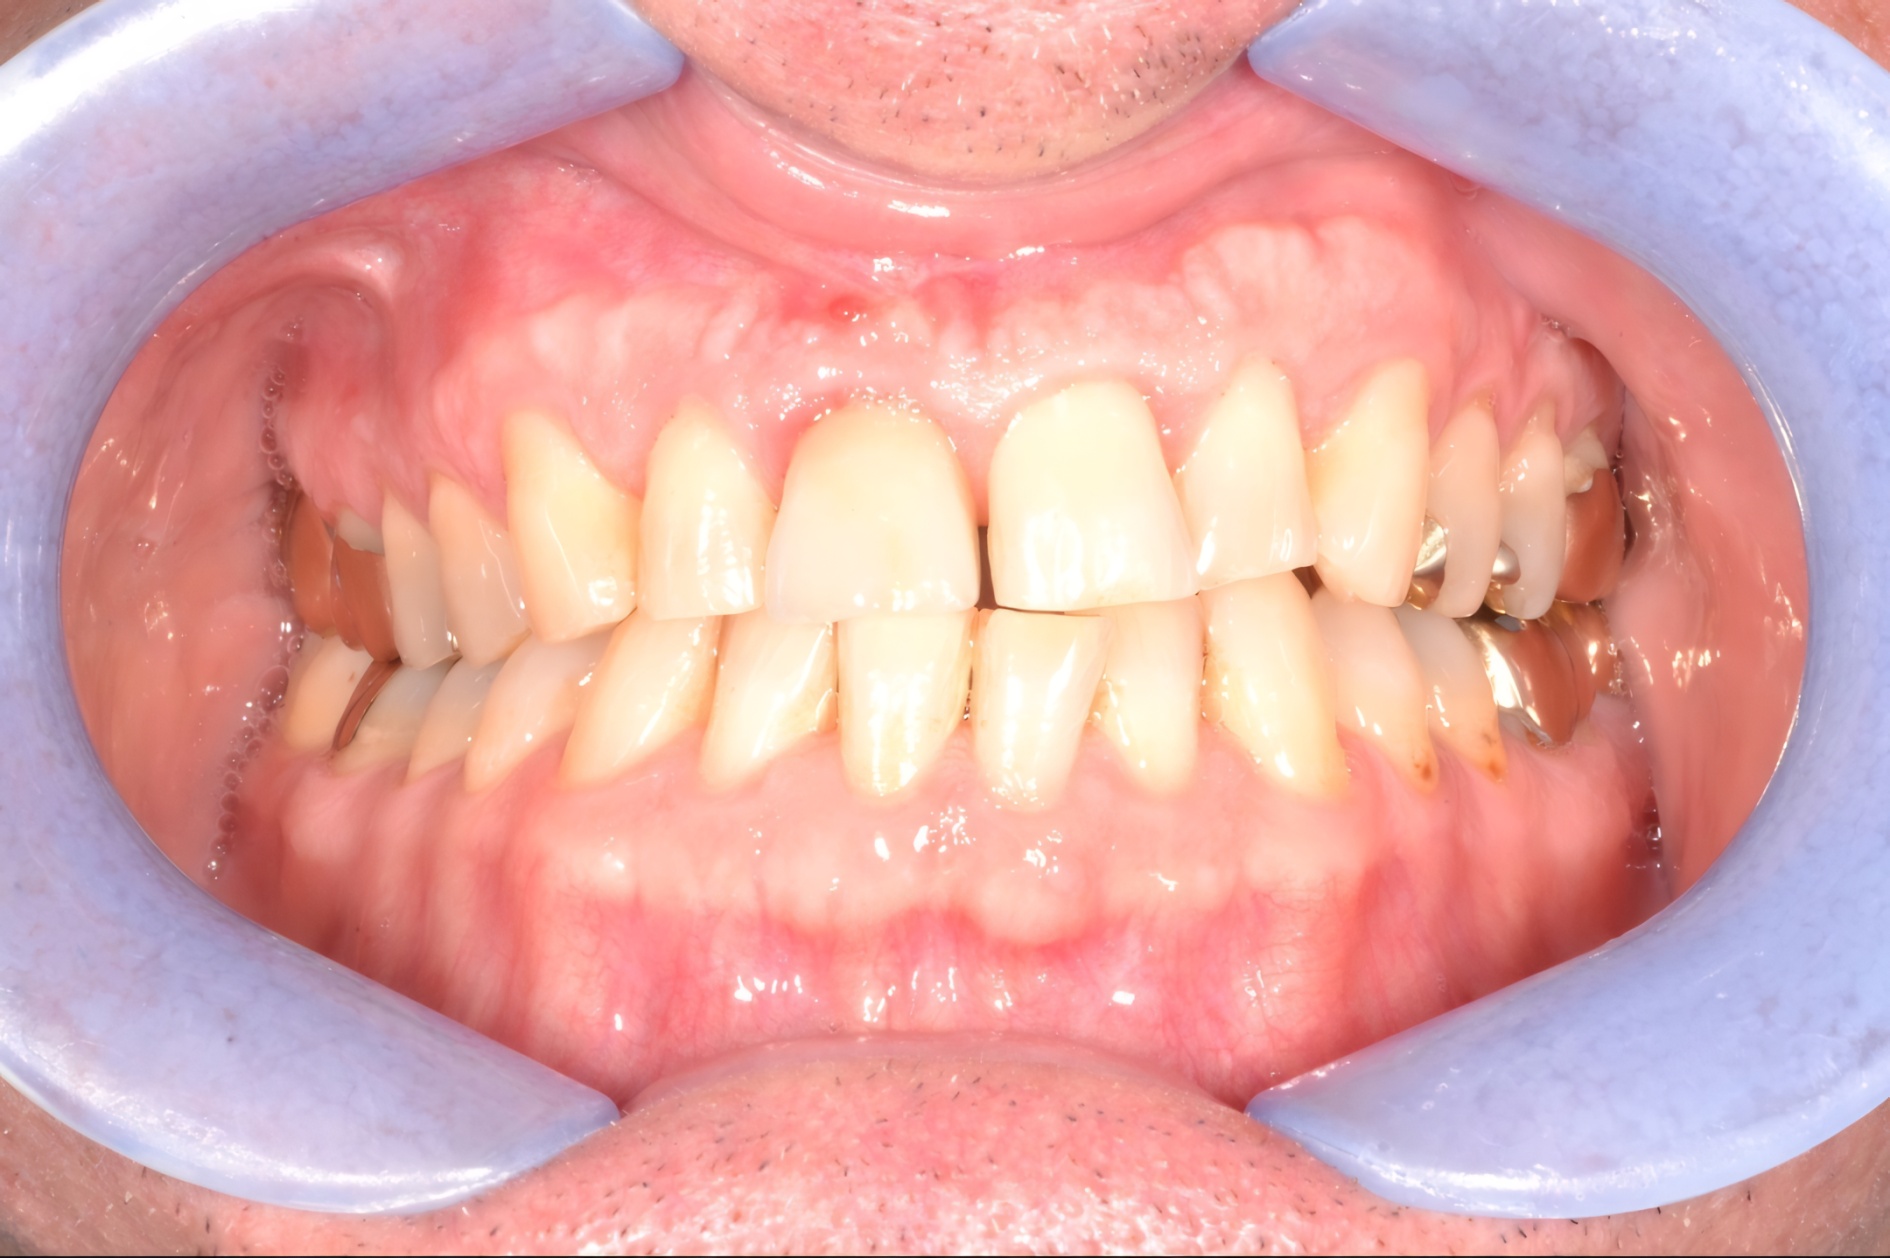

Ein 55-jähriger Soldat stellte sich in der Abteilung für Zahnmedizin des Bundeswehrkrankenhauses Berlin zur Routineuntersuchung vor. Anamnestisch gab er vollständige Schmerzfreiheit an. Im visuell-taktilen Befund imponierte Zahn 11 mit einer vestibulären Fistelbildung sowie einer knöchernen Auftreibung. Cervikalwärts der bestehenden Kronenversorgung zeigte sich verfärbtes Wurzeldentin.

Auf perkussiven Reiz gab der Patient keinen Dolor an, die Sensibilitätsprobe mittels Kältetest an den Nachbarzähnen fiel positiv aus. Es lagen keine pathologischen Sondierungstiefen vor, und die Soundingprobe war negativ. Es handelte sich daher um eine isolierte endodontische Läsion, nicht um eine Paro-Endo-Läsion.